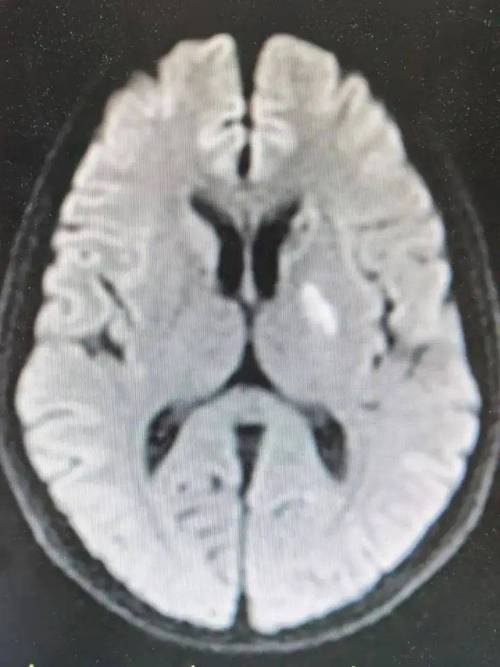

- 快速检查与评估: 医生会立即进行体格检查,并在最短时间内安排头颅CT等影像学检查,以排除脑出血,确诊脑梗死。